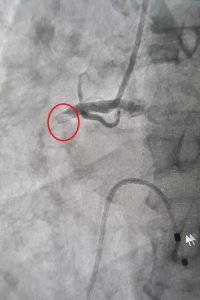

Bệnh nhân nữ 54 tuổi, quê Thanh Hoá bị đau cột sống thường xuyên, không thể ngồi lâu, hạn chế mọi vận động trong cuộc sống sinh hoạt hằng ngày do lao cột sống. Hiện tại, sau hơn 1 tháng phẫu thuật điều trị lao cột sống tại Bệnh viện Đa khoa Xuyên Á TP.HCM (BVXA), bệnh nhân đã hồi phục tốt, giảm đau lưng rõ rệt, đi lại dễ dàng mà không cần hỗ trợ.